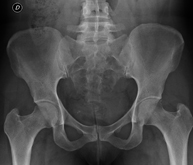

Procediment que permet, mitjançant l'ús de raigs X, i després d'injectar un contrast a l'interior de l'articulació, detectar lesions d'aquestes articulacions (cartílag, os, tendons, etc. ) segons la distribució del contrast. - RX Pelvis

Procediment que usa els raigs X a través de la qual s'obtenen imatges de la pelvis per al seu estudi, especialment dels ossos pèlvics. - RX Edat òssia

Estudi que usa els raigs X a diferents parts del cos (crani, columna, costelles, pelvis, húmers i fèmurs) per descartar que existeixen lesions en aquests ossos. Indicacions: estudi del mieloma múltiple, gammapaties monoclonals, metàstasi. - RX Sacroilíaques

Procediment que mitjançant l'ús de raigs X permet l'estudi de les articulacions sacroilíaques i descartar que existeixen malalties inflamatòries, traumàtiques o degeneratives.